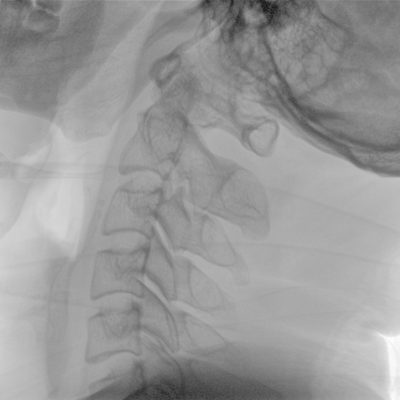

Clinical picture

临床图片

骨科: 经皮锥体成形术、经皮椎间盘臭氧治疗术、胸脊椎固定、骨活检、腰椎内固定术等。